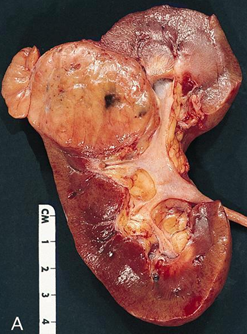

Đại thể

Thường là khối u vỏ thận một bên và đơn ổ, kích thước trung bình khoảng 7 cm. Khối u thường có ranh giới rõ, được bao quanh bởi giả bao u, phát triển theo kiểu đẩy nở và lồi ra từ vỏ thận. Hình thái đại thể đa dạng với thành phần đặc và nang, kèm các vùng xơ hóa màu xám và các ổ xuất huyết mới hoặc cũ màu nâu; hoại tử và biến đổi nang gặp thường xuyên. Khối u có màu vàng ánh kim do hàm lượng lipid cao; các khối u có độ mô học cao hơn có thể không có màu vàng do hàm lượng lipid và glycogen thấp hơn. Các vùng mềm, dạng thịt có thể phản ánh sự hiện diện của biệt hóa dạng sarcomatoid. Thường xuyên ghi nhận xâm lấn tĩnh mạch thận và xoang thận. Tổn thương hai bên và đa ổ là đặc điểm gợi ý bệnh lý di truyền.

Về phân giai đoạn, các khối u có kích thước lớn hơn 7 cm hầu như luôn xâm lấn mỡ xoang thận; nếu không quan sát thấy xâm lấn ở các khối u lớn, cần tiến hành xem xét lại đại thể bổ sung. Xâm lấn bao thận được đặc trưng bởi sự tiến triển không đều và gián đoạn của khối u vào mô mỡ quanh thận kèm theo mất đường viền ngoài lồi đều, nhẵn của thận; khối u lồi đều, nhẵn và được bao phủ bởi giả bao ung thư không được xem là xâm lấn mỡ quanh thận. Để chẩn đoán xâm lấn, tế bào u phải tiếp xúc trực tiếp với mô mỡ hoặc xâm nhập dạng các lưỡi không đều vào mô quanh thận, có hoặc không kèm phản ứng xơ sinh. Xâm lấn xoang thận là con đường lan tràn ngoài thận thường gặp nhất và thường xảy ra trước xâm lấn bao thận; khác với bao thận, xoang thận không được ngăn cách với nhu mô thận bằng một bao xơ riêng biệt. Không được coi là xâm lấn thực sự nếu khối u vẫn được ngăn cách với các cấu trúc xoang bởi một viền nhu mô thận; được coi là xâm lấn xoang thận khi khối u lồi rõ vào mô mỡ xoang thận vượt quá nhu mô thận, kể cả khi vẫn được bao phủ bởi mô liên kết thưa. Việc khối u bao quanh các cấu trúc mạch máu hoặc bạch mạch lớn là dấu hiệu gợi ý xâm lấn mỡ xoang thận. Xâm lấn mạch máu có thể biểu hiện dưới dạng các nốt u trong xoang thận; trong trường hợp lòng mạch bị bít một phần, sự hiện diện của một lớp nội mô đơn độc phủ lên bề mặt khối u không loại trừ xâm lấn mạch máu. Xâm lấn tĩnh mạch nhỏ thường hàm ý xâm lấn tĩnh mạch lớn, và xâm lấn xoang thận thường đồng nghĩa với xâm lấn tĩnh mạch thận, do đó cần được thăm khám và đánh giá một cách thận trọng.

Hình 2. ccRCC đã xâm lấn mạc Gerotta (pT4)

Hình 3. ccRCC có màu vàng, giới hạn ở thận (pT1b)

Hình 4. ccRCC đa ổ, với diện cắt đại thể loang lổ, khối u màu vàng óng xen kẽ các vùng xơ hóa và xuất huyết. Các vùng mềm, dạng thịt, màu nâu nhạt đến trắng xám trong khối u có thể gợi ý sự biệt hóa sarcomatoid.